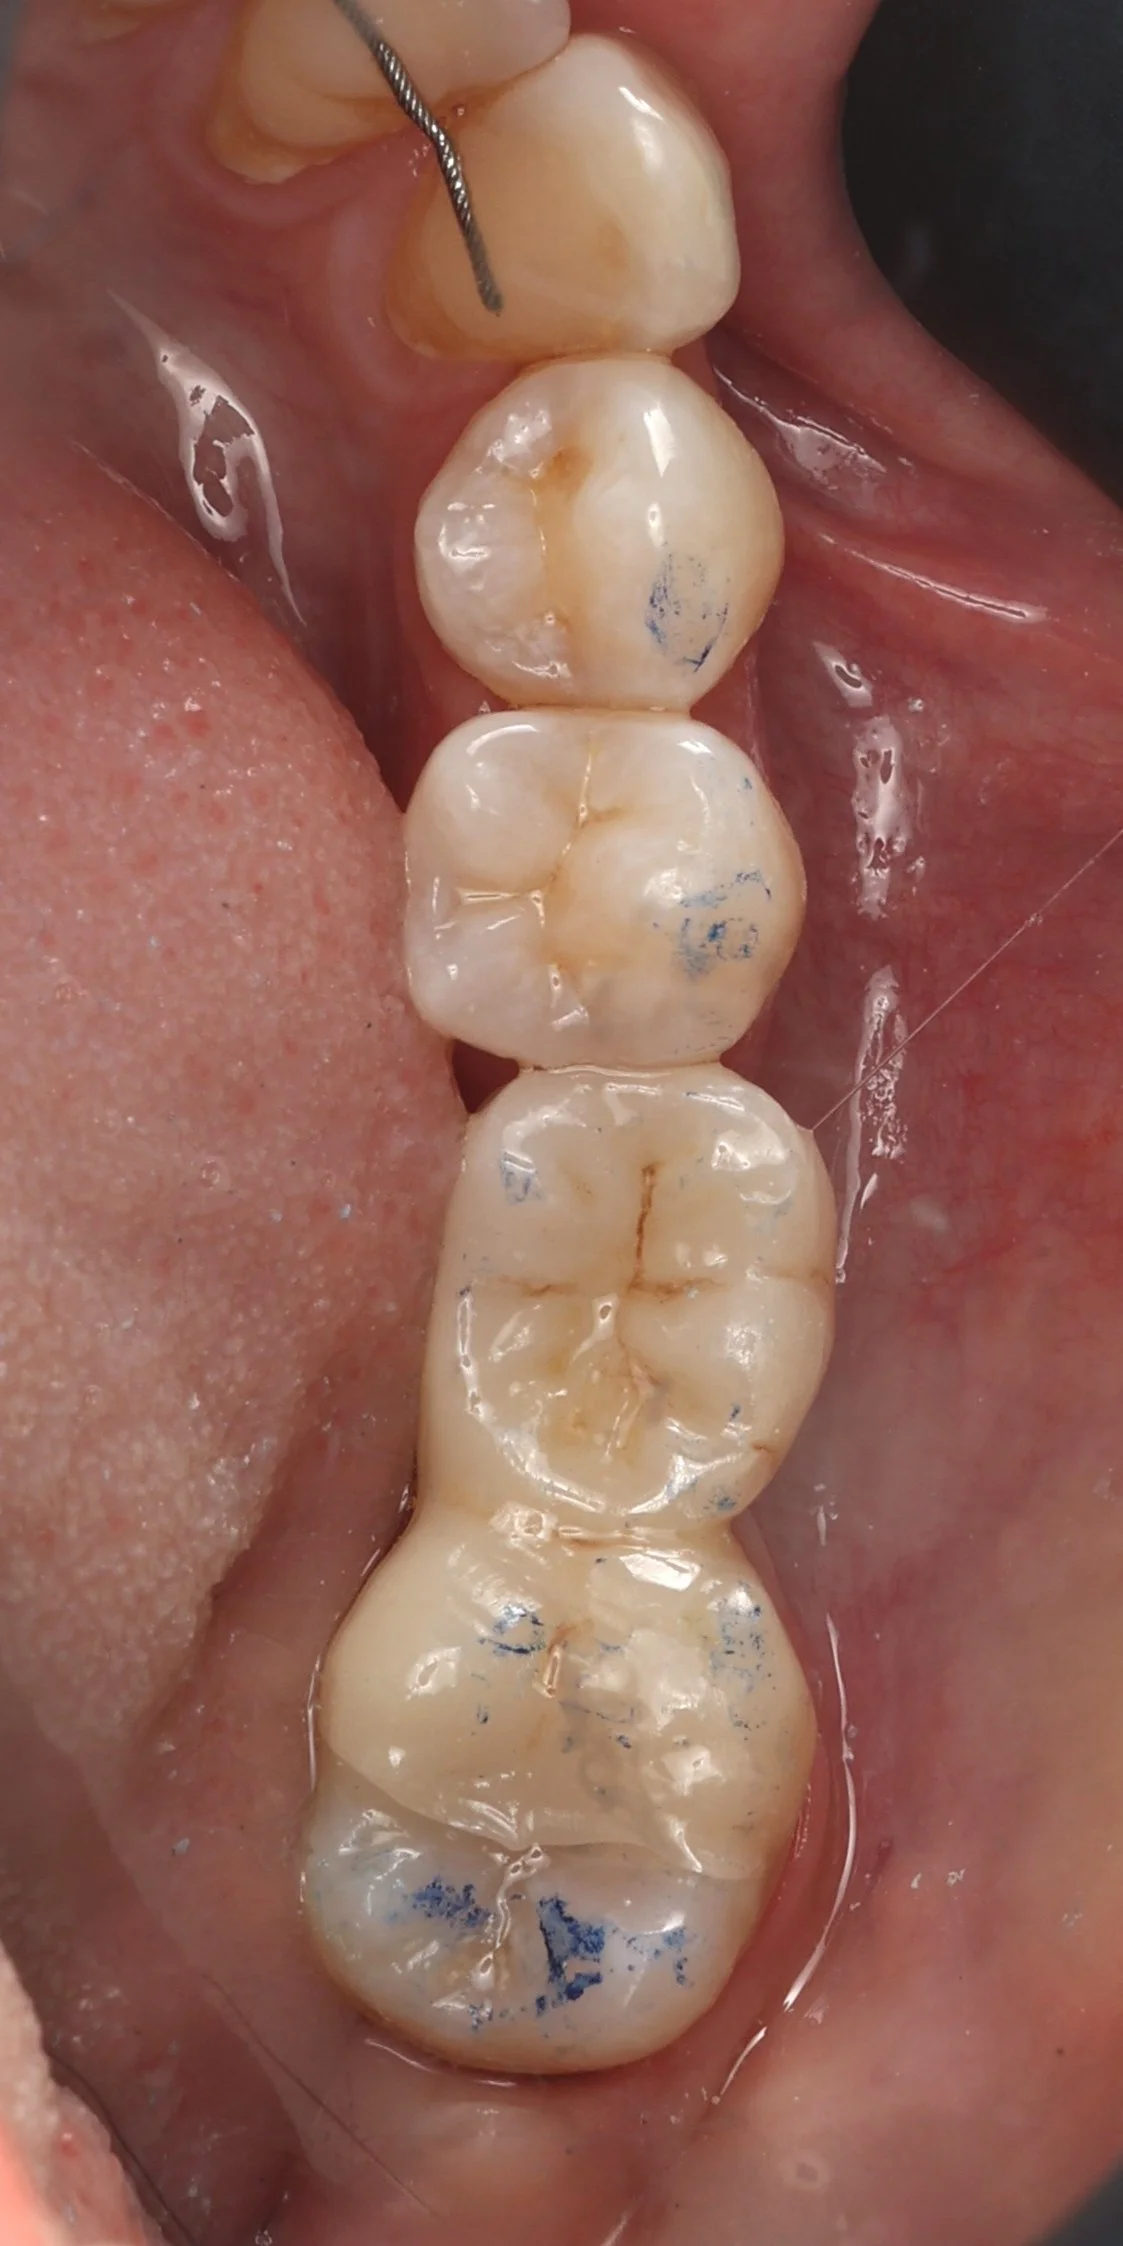

Relativement récents, les bridges collés cantilever postérieurs constituent une alternative fixe, fiable et véritablement minimalement invasive aux implants dans les secteurs postérieurs. Cette thérapeutique qui repose sur des indications bien précises est parfois débattue avec passion sur les réseaux sociaux ou dans les congrès scientifiques. Cependant des études cliniques existent, tout comme des recommandations validées dans des journaux internationaux. Leur succès repose sur des préparations et des principes biomécaniques rigoureux, pourtant simples à intégrer au quotidien. Cette intervention propose un guide clair et opérationnel incluant indications, étapes clés, protocoles d’adhésion et réglages occlusaux pour les mettre en œuvre avec confiance et reproductibilité.